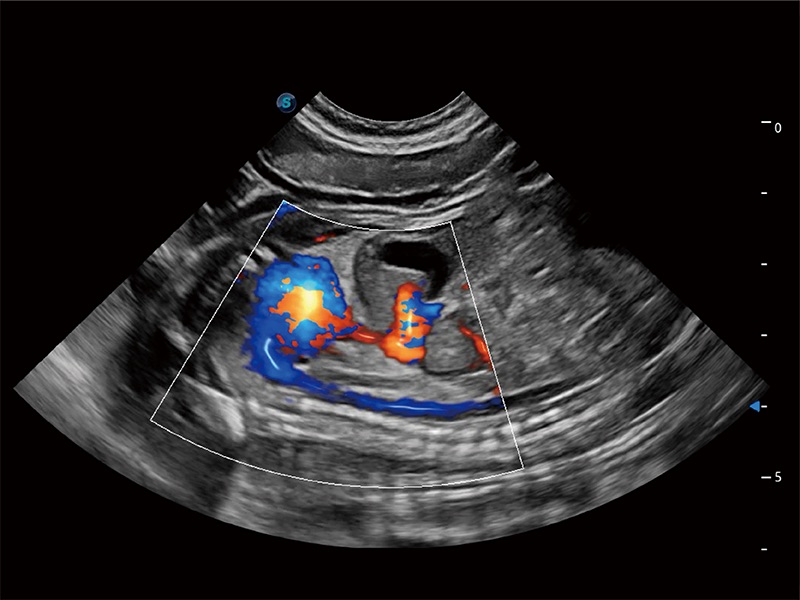

(犬)胎儿主动脉弓立体血流

(犬)胎儿四腔心